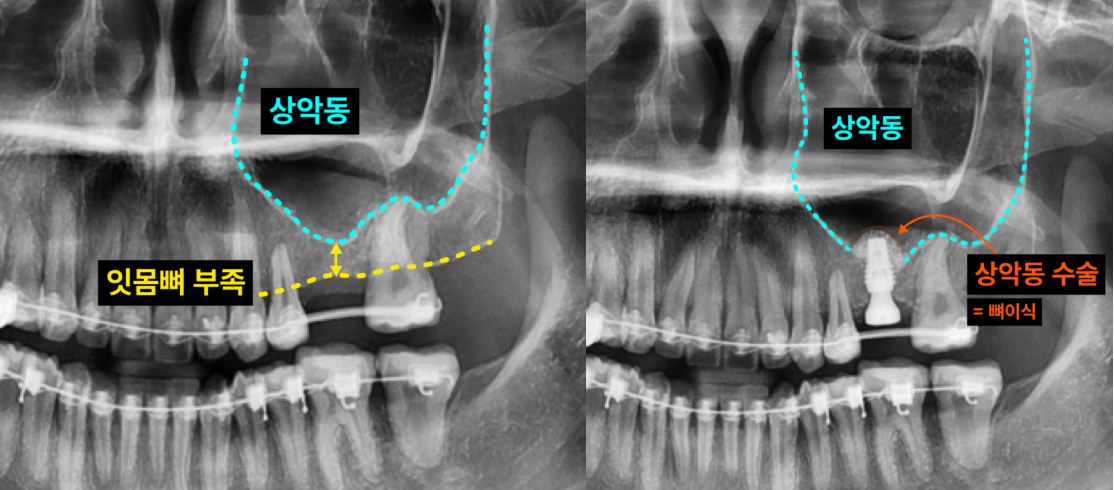

"윗 잇몸뼈가 부족해서 상악동 수술이 필요하다"는 이야기를 들어본 적 있으신가요? 임플란트 식립 시 윗니 어금니 부위의 잇몸뼈가 충분하지 않을 때 필요한 시술이 바로 상악동 수술(상악동 거상술, 상악동 뼈이식)입니다. 이백점치과는 고난이도 상악동 수술도 안전하고 성공적으로 진행하여 환자분들께 건강한 임플란트를 선사합니다. CASE. 20대 여성 환자 "잇몸뼈가 부족해요" 임플란트 고민 ○ 환자분의 고민: 왼쪽 위 어금니 임플란트를 희망하며 교정치과로부터 의뢰되어 내원하셨습니다. ○ 진단: 임플란트 식립에 필요한 잇몸뼈(일반적으로 8~10mm 길이의 임플란트 식립)가 4~5mm로 턱없이 부족 한 상태였습니다. ○ 치료 계획: 부족한 잇몸뼈를 확보하기 위해 상악동 막을 안전하게 들어 올린 후 뼈이식을 진행하는 상악동 수술 을 계획했습니다. ![]() 이백점치과의 정교한 상악동 수술 과정 상악동 수술은 상악동 막을 손상 없이 거상하고 뼈이식을 진행하는 정밀한 시술입니다. 1. 정밀 진단: CT 촬영을 통해 남아있는 잇몸뼈의 양과 상악동의 상태를 면밀히 분석합니다. 2. 상악동 거상 및 뼈이식: 부족한 잇몸뼈 부위에 상악동 막을 조심스럽게 들어 올린 후 충분한 양의 뼈를 이식합 니다. 이로써 임플란트 식립에 필요한 충분한 잇몸뼈 공간을 확보합니다. (예: 4~5mm 남아있던 잇몸뼈에 4~5mm 추가 뼈이식으로 8~10mm 확보) 3. 임플란트 식립: 뼈이식을 통해 확보된 충분한 잇몸뼈에 임플란트를 정확한 위치와 각도로 식립합니다. ![]() 성공적인 결과와 빠른 회복 수술 후 CT 촬영을 통해 기존 잇몸뼈 위로 상악동이 잘 올라가고 새로운 뼈가 성공적으로 이식되었음을 확인했습 니다. 또한 임플란트가 정확하게 식립되었음을 검증했습니다. ![]() 상악동 수술 후 임플란트 크라운(보철물)은 보통 3~6개월 뒤에 완성됩니다. 이 기간은 환자분의 남아있는 잇몸뼈양에 따라 달라질 수 있습니다. 본 환자분은 4개월 뒤 성공적으로 본을 뜨고 임플란트 크라운까지 장착 완료하여 건강하고 기능적인 치아를 되찾았습니다. ![]() 상악동 수술, 숙련된 의료진에게 맡겨야 하는 이유 상악동 수술은 출혈, 상악동염, 상악동 천공 등 다양한 합병증이 발생할 수 있는 고난이도 시술입니다. 따라서 외과 적인 수술 경험이 풍부하고 임플란트 보철에 대한 깊이 있는 이해를 가진 숙련된 의료진을 만나는 것이 무엇보다 중요합니다. 이백점치과는 수많은 임상 경험과 정교한 기술력을 바탕으로 고난이도 상악동 수술까지 안전하게 진행하며, 환자분들이 믿고 맡길 수 있는 최상의 진료를 제공합니다. 당신의 건강하고 아름다운 미소를 위해 이백점치과가 함께하겠습니다. |